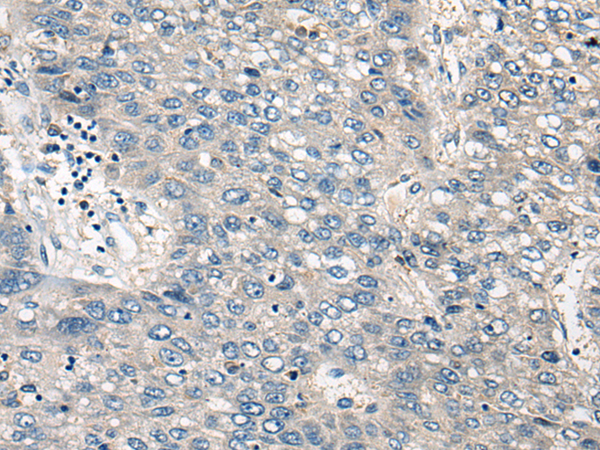

ELISA, IHC |

IHC positive control: |

Human liver cancer |

IHC Recommend dilution: |

25-100 |